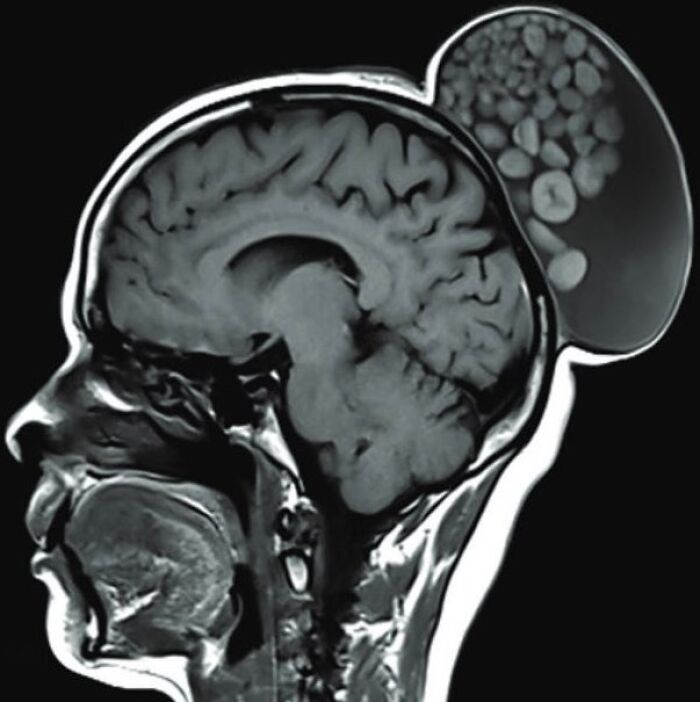

A 12-year-old immigrant female was admitted in the dermatology department with multiple brown lesions on the trunk and face and a large cerebriform plaque on the right side of her scalp.

She was born with multiple brown papules and nodules on the trunk and face and a brown patch on the right side of her scalp. She reported an increase in the size of the lesions on her body and face over time and there was no associated pain or itching. According to history given by her parents, the lesion on the scalp was a small brown flat patch at birth and had increased in size and thickness over the last 8 years and in the past 5 years it had become nodular and cerebriform. The patient complained of intense itching and discharge which had recently become malodorous.

Her birth and developmental history were normal.

In physical examination, her developmental and nutritional status was normal. The head circumference was in normal range and her neurologic, cardiovascular, musculoskeletal, and ophthalmic examinations were normal

The mass on the scalp sized 22 cm × 18 cm × 2.5 cm approximately with a nodular surface spread across the right side of the scalp.

52-year-old woman presented with a painless, gradually enlarging scalp swelling

A 15-year-old female presented with a 8 cm x 7 cm, ovoid-shaped, hairy lesion on the right side of her face The palm-sized solitary lesion was present since birth and enlarged as she grew .An interview confirmed no personal or family medical history of melanoma or any form of cancer. The patient denied pain, pruritis, functional problems, or limitations in facial expression due to the lesion

A 57-year-old female presented with a rapidly growing ellipse-shaped nodule on her scalp for two years .The mass did not regress with time and was filled with serous fluid. The patient had a medical history of diabetes and hypertension, and her family history was not significant. Physical examination revealed an oval-shaped mass with a central scar, no discharge, no fluctuation, and painless.

The gross pathological description includes a skin ellipse measuring 1.5 x 1.2 × 0.4 cm with a raised skin lesion and a central crater measuring 1.1 cm.

Microscopically, sections showed skin-abundant pilosebaceous follicles with dilated infundibulum containing lamellated keratin and lined by stratified squamous epithelium with peripheral basal cells and no cytologic atypia

Bobble-head doll syndrome in an infant with an arachnoid cyst

Bobble-head doll syndrome is a rare neurological movement disorder in which patients, usually children around age 3, begin to bob their head and shoulders forward and back, or sometimes side-to-side, involuntarily, in a manner reminiscent of a bobble head doll. The syndrome is related to cystic lesions and swelling of the third ventricle in the brain. Symptoms of bobble-head doll syndrome are diverse but can be grouped into two categories: physical and neurological. The most common form of treatment is surgical implanting of a shunt to relieve the swelling of the brain.

A 1.5-year-old girl presented to the pediatric clinic with the chief complaints of gradual onset excessive head nodding (side-to-side movement) for 3 months. Movements increased with walking, emotions, and stress; decreased during periods of concentration; and were absent during sleep. There were no other complaints or headaches. There was no other significant history.

The child was alert, with normal cognitive function. Neurological examination was normal. Initial laboratory assessment including CBC, hepatic and renal function, and endocrine function tests were normal.

Cranial MRI demonstrated a large left-hemispheric cystic process with a midline shift, well-defined thin-walled suprasellar arachnoid cyst measuring 3 × 5 × 7 cm that obstructed the foramina of Monro, with resulting hydrocephalus ventriculomegaly. Based on the cranial MRI and symptoms, a diagnosis of a suprasellar arachnoid cyst with BHDS was made. The patient underwent endoscopic cystoventriculostomy and cystocisternostomy for the suprasellar arachnoid cyst. During the 6 months of follow-up, the head bobbing disappeared completely, and her growth was normal.

Despite the rareness of bobble-head doll syndrome, it is considered an important condition that must be investigated early to detect the cause and treated promptly to avoid potential complications.